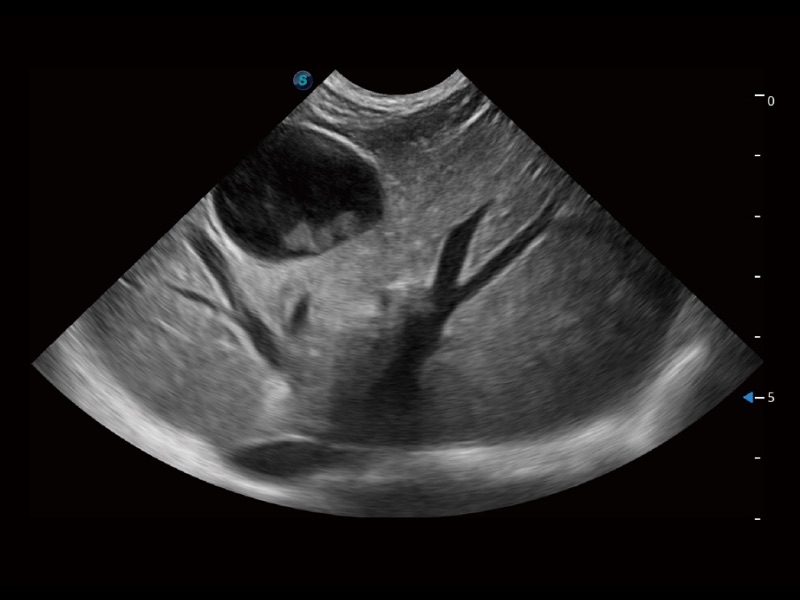

大型犬、馬科、農(nóng)場(chǎng)動(dòng)物及大型異寵動(dòng)物

通過創(chuàng)新的 Matrix E自適應(yīng)濾波器和超長(zhǎng)時(shí)間域算法,極大提升超低速微細(xì)血流的檢出能力,同時(shí)更精準(zhǔn)地濾除軟組織和噪聲信號(hào),為獸用醫(yī)生提供以往無法通過常規(guī)血流獲得的疾病診斷信息。